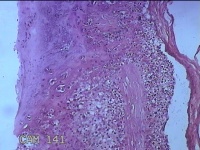

胎盘组织

性别

女

年龄

35岁

临床诊断

胎膜早破 早产

一般病史

停经36+1周,阴道流液3天。

标本名称

大体所见

灰白暗红色胎盘组织18x15.5x2.3㎝一个,表面光滑,血管清晰,颜色发暗,绒毛面结节状,轻度糜烂,表面有少许凝血块,切面见绒毛内有部分淤血,边缘蜕膜可见多个小血肿,脐带15x1.5x0.8㎝,切断脐带,见脐血管内有凝血块。